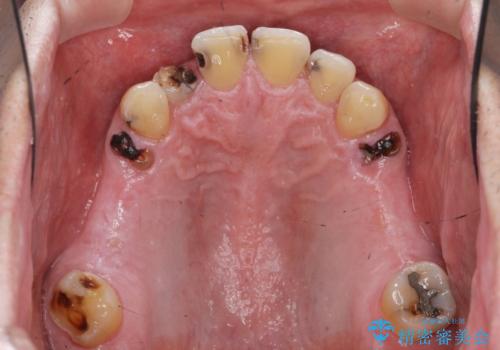

インプラント治療・セラミック治療を含む 全顎的虫歯治療

- 「 仕事が忙しく、虫歯を放置しすぎてしまった。この際全てきっちりと治したい。」と来院されました。

・歯の欠損

・虫歯

・深い虫歯

・欠損の放置による対合歯の挺出

・咬合平面の乱れ

・感染根管

以上のような問題を、徹底的な虫歯治療、歯周外科、インプラント治療、部分矯正治療、精密根管治療を用いてひとつずつ解決ししっかりと長期的に食事を楽しめるような口腔内環境の再構築を目指します。